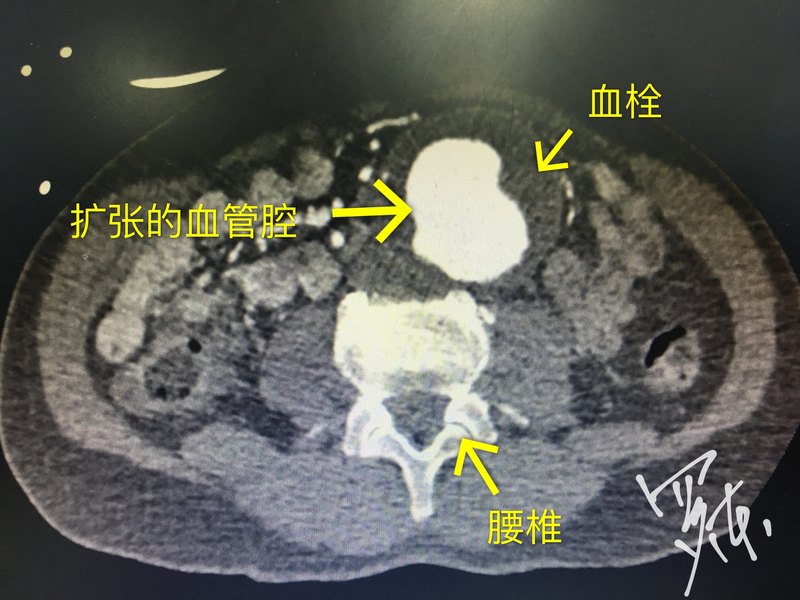

今天總共做了3個(gè),選這個(gè)大的給大家看看,大概了解一下腹主動(dòng)脈瘤和其介入治療。 介入手術(shù)治療血管疾病最大的優(yōu)勢(shì)就是微創(chuàng),手術(shù)一個(gè)小時(shí)左右完成,70多歲的大爺明天就可以下地行走。這樣的手術(shù)今年已經(jīng)完成過(guò)百例了。